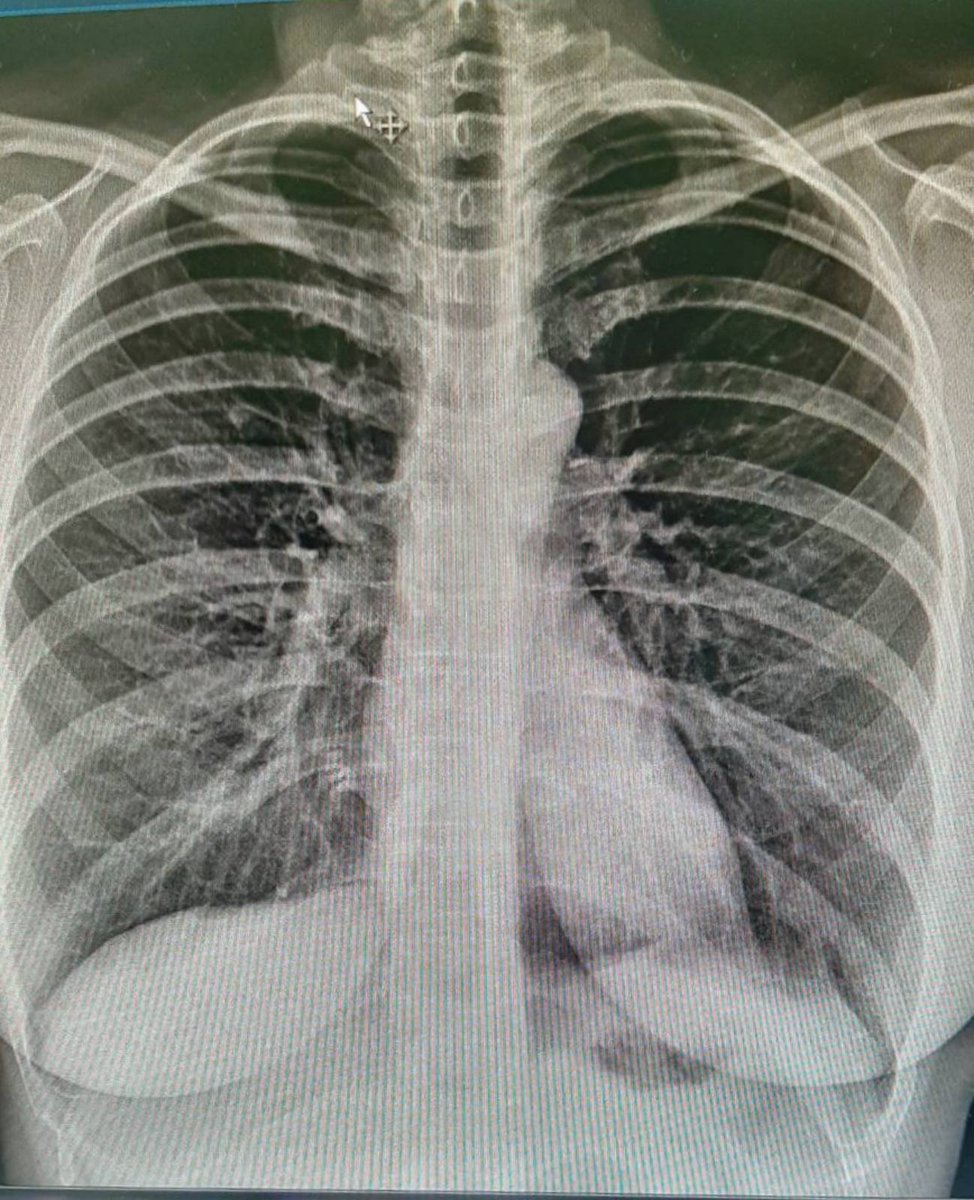

ugrožena', ali je pojasnila i kako dolazi do izuzetno teških slučajeva u kojima se 'čak i za nekoliko sati razviju ekstremno teške pneumonije'.Zabrinjavajuće su slike koje vidimo u medijima – rtg snimke oboljelih osoba koje ljekari opisuju sa ”pacijent gotovo i nema pluća”⬇️.

Vakcinisani mnogo rijeđe obolijevaju od covida-19. Covid može da prođe kao jako blag, ali često znaju da se jave i ekstremno teški oblici, gdje se čak i za nekoliko sati naprave užasne pneumonije koje bukvalno razaraju pluća. Koronavirus ima osobinu da oštećuje endotel krvnih⬇️

i dovodi do trombotičkih poremećaja na plućima i srcu, u mozgu. To je veoma kompleksan mehanitzam poremećaja koji uvodi pacijenta u kritična stanja opasna po život. Ako bolest traje duže od mesec dana, onda govorimo o